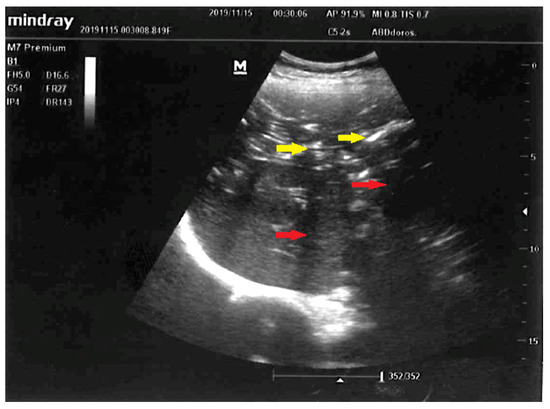

Sonographic Images of Hepatic Portal Venous Gas in a Patient with Gastrointestinal Ischemia